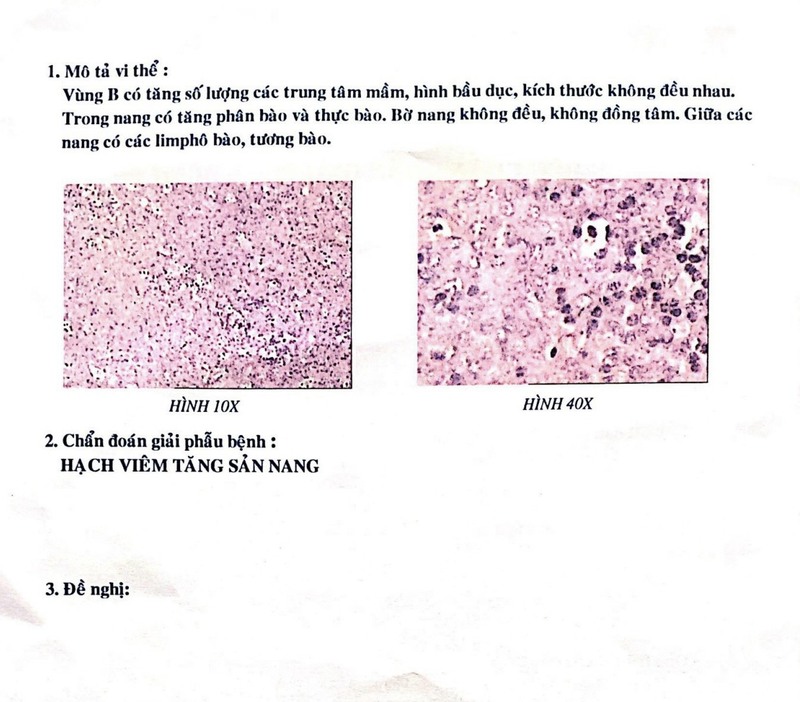

IX. MÔ HỌC

- Sự mở rộng của trung tâm mầm, tỷ lệ phân bào từ trung bình đến cao, vùng vỏ rõ rệt, sự phân cực của trung tâm mầm, các nang có hình dạng và kích thước khác nhau, đại thực bào cơ thể có thể sờ thấy và hỗn hợp các loại tế bào. ở trung tâm mầm bệnh

- Các hạch bạch huyết có tăng sản nang phản ứng cho thấy mật độ nang thấp hơn so với lymphoma thể nang

- Kết quả sinh thiết lõi : hạch tăng sản nang

- Kết quả giải phẫu bệnh: hạch tăng sản nang